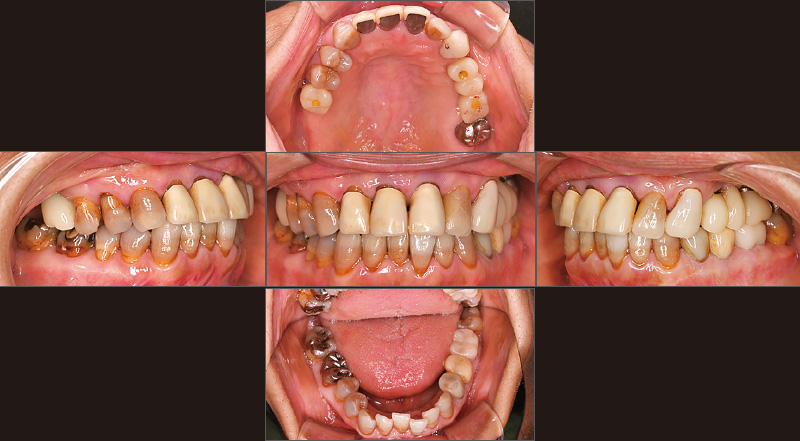

図1 初診時。60代女性。2019年9月、「奥歯でものが噛めない」という主訴で当院を来院。義歯治療によって咀嚼機能の回復を図った。 -